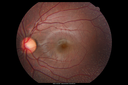

12 year old female She went last December for her regular checkup and spots were noted on the retina in the periphery. Her vision is fine and there is no family history of retinal disease. She has difficulty seeing at night and finding her way in a dark theater. VA OD: Dcc20/20-1 NccJ1+ VA OS: Dcc20/20 NccJ1+

Fundus Albipunctatusvista 962 veces12 year old female with normal vision. She has 4 siblings all of whom have either white spots or spots on IR. Genetic testing by parents was deferred.00000